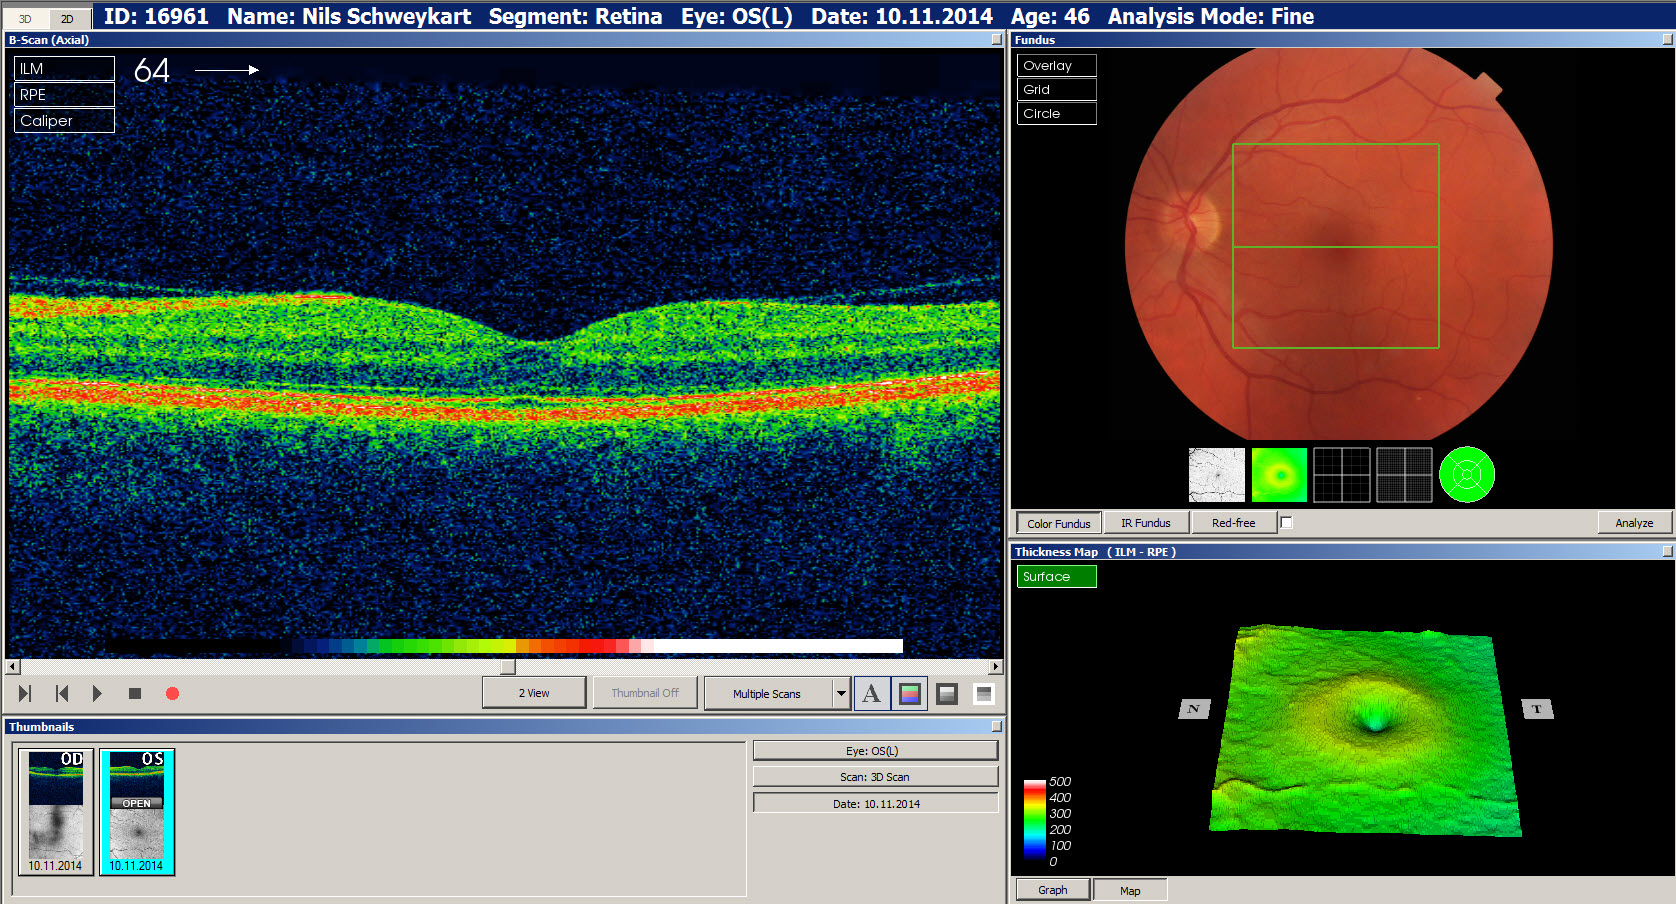

- Optische Kohärenztomographie ("OCT")